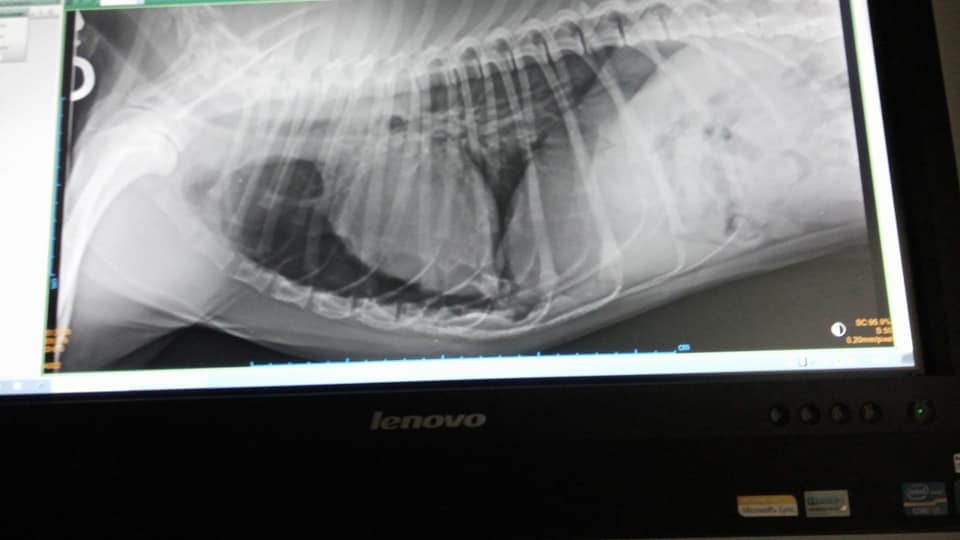

Dieser arme Hund wurde auf einer Straße in Spanien angefahren und einfach liegengelassen. Leider ein alltägliches Bild in Spanien. Zum Glück wurden unsere Tierschützerinnen informiert und haben Osito, wie sie den Rüden genannt haben, gleich in die Tierklinik gefahren. Er wurde geröngt und wird nun in der Klink versorgt. Beide Vorderbeine und einige Rippen sind gebrochen und Osito hat einen Riss im Kopf. Trotz der großen Schmerzen wedelt dieser liebe Hund bei jedem lieben Wort und jeder Streicheleinheit mit seiner Rute. Osito ist ein sehr lieber und geduldiger Patient, der es verdient hat, dass wir ihm helfen. Der Klinkaufenthalt und die nötige Operation kosten ca. 800 €. Unsere Tierschützerinnen benötigen dringend finanzielle Hilfe bei der Deckung der Kosten, die nun anfallen. Vielleicht gibt es ja einige tierliebe Menschen, die sich mit einer, und sei es noch so kleinen, Spende, an der Operation und dem Klinkaufenthalt beteiligen möchten. Jede Spende wird umgehend nach Spanien weitergeleitet. Wir stellen gerne eine Spendenbescehinigung aus. Osito, wir lassen dich nicht im Stich.